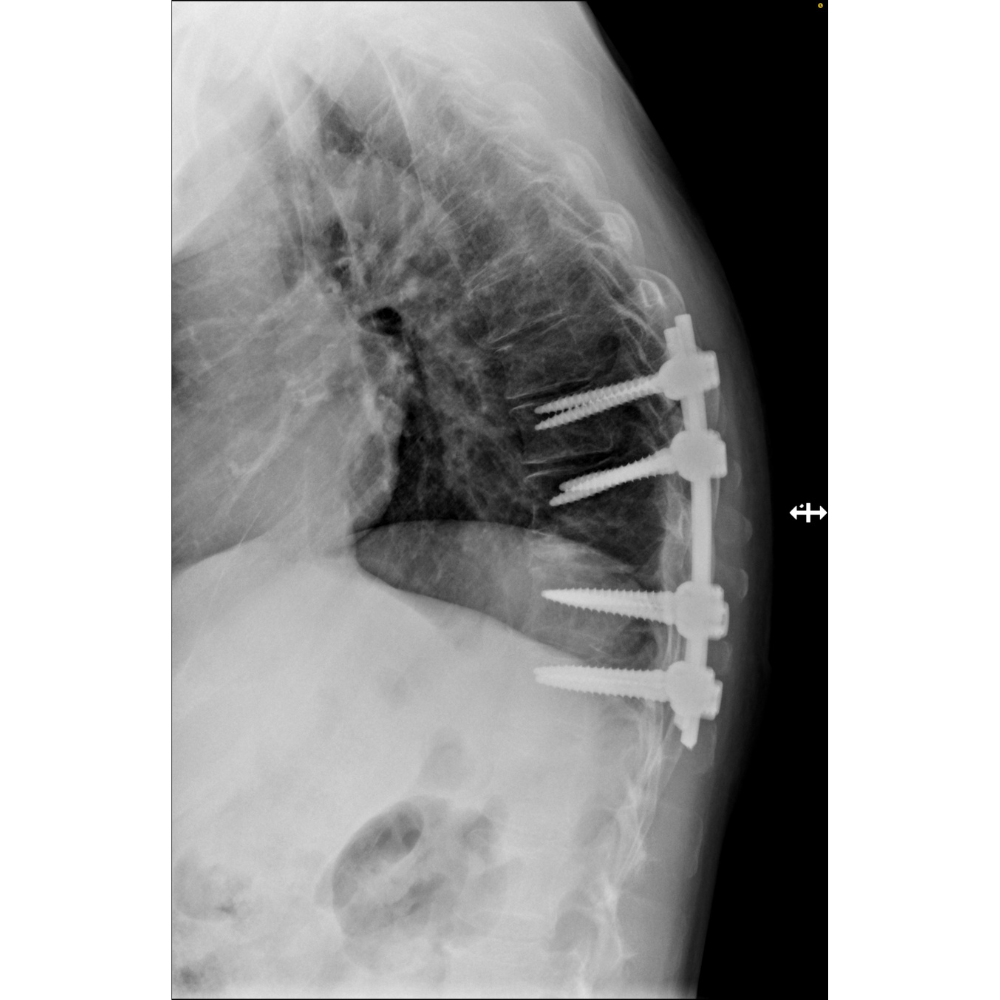

3. Spinal Stabilization: Use of rods, screws, or bone grafts to restore stability after tumor removal.

1. Pre-Surgical Evaluation: Includes imaging studies (MRI, CT, or X-rays), biopsy (if needed), and a thorough assessment of overall health.